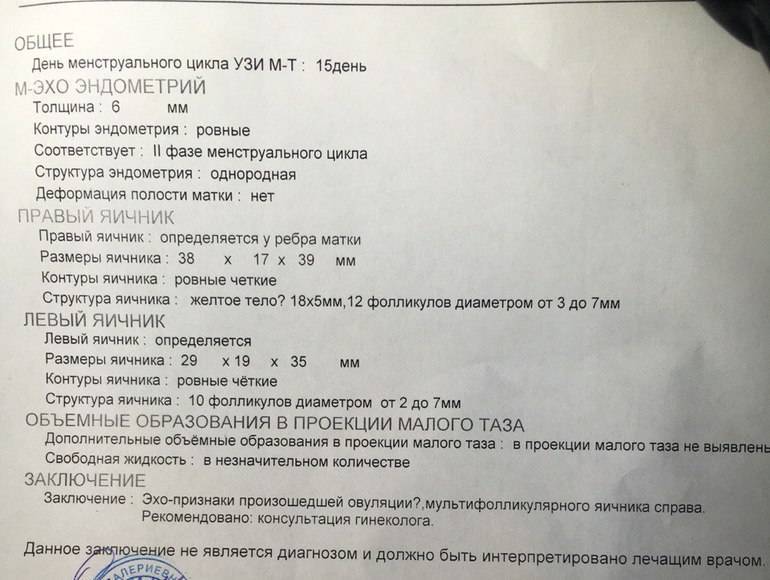

Почему разные заключения на УЗИ?